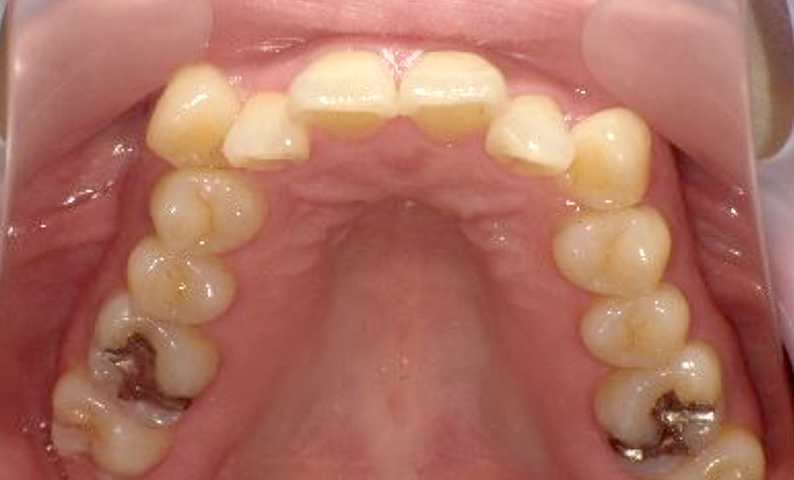

症例_003 上下顎の部分矯正

治療期間:12ヶ月金額:54万円+税男性八重歯前歯のガタガタ

| Before | After |

|---|---|

|